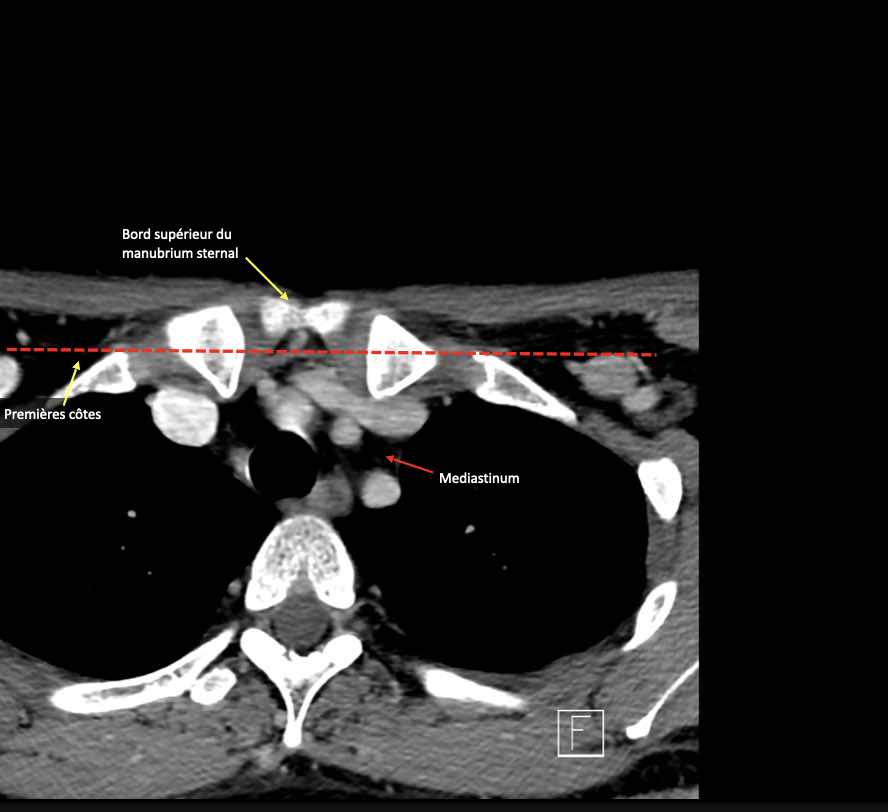

- Cán xương ức

IV – Tĩnh mạch cảnh dưới và hố thượng đòn trong

Ranh giới giữa tầng IVa và IVb được xác định tùy ý tại vị trí 2 cm phía trên khớp ức đòn.

Tầng này chứa các hạch thượng đòn bên nằm trong phần tiếp nối của các hạch tam giác cổ sau (tầng Va và Vb) từ các mạch máu cổ ngang xuống đến giới hạn được xác định tùy ý tại vị trí 2 cm phía trên cán ức.